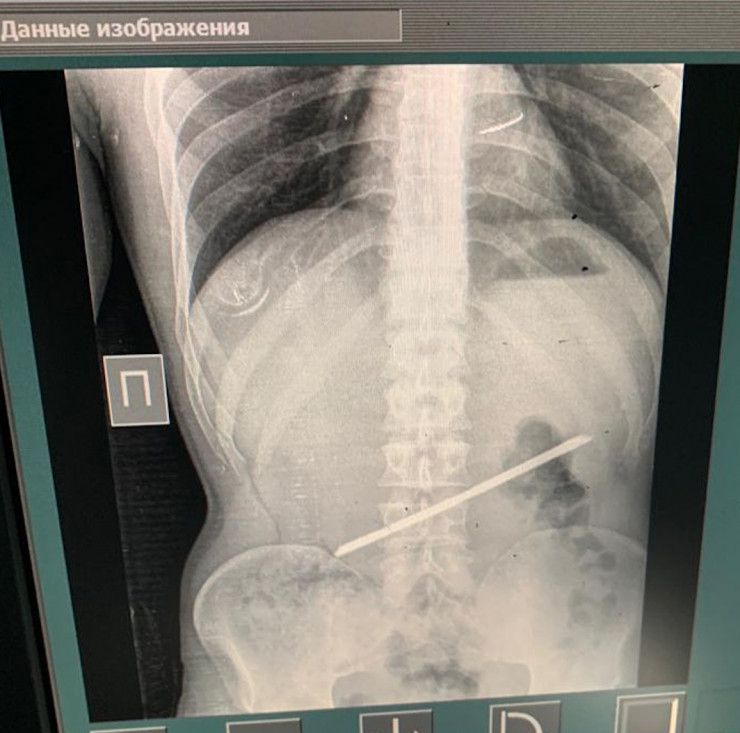

Хирурги в Алматы извлекли 25-сантиметровую арматуру из желудка мужчины, передает Tengrinews.kz со ссылкой на пресс-службу Управления общественного здоровья Алматы.

С арматурой в желудке мужчина прожил 2,5 года и только сейчас обратился с проблемой к врачам. Для врачей неотложной помощи извлечение инородного тела - операция из разряда несложных. За 54 минуты операционная бригада справилась с задачей.

"28 сентября он сам пришел в больницу с жалобами на острые боли в эпигастральной области. Со слов пациента, более двух лет назад он находился в следственном изоляторе, где и проглотил арматуру. Слова пациента подтвердились в результате рентген-диагностики, мужчину сразу взяли на операцию, проведены: лапаротомия, гастротомия, удаление инородного тела. Операция прошла успешно, пациент переведен в палату пробуждения", - рассказал хирург приемного отделения Городской клинической больницы № 4 Темирхан Кожахметов.

Уникальным врачи называли тот факт, что более двух лет металлический предмет в желудке не доставлял проблем.

"Инородное тело не мигрировало и не повредило стенки желудка. Перфорация и пролежни - самые распространенные из осложнений при подобных случаях. Перфорация - это прорыв инородного тела в свободную брюшную полость с поступлением в нее желудочно-дуоденального содержимого", - сообщили в УОЗ Алматы и предоставили список операционной бригады.